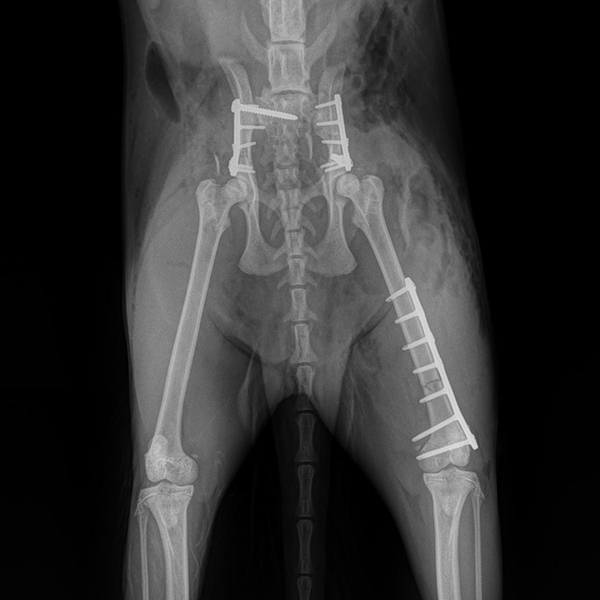

Case Overview In November 2025, Skeeter, a 14-week-old Doodle puppy weighing ...